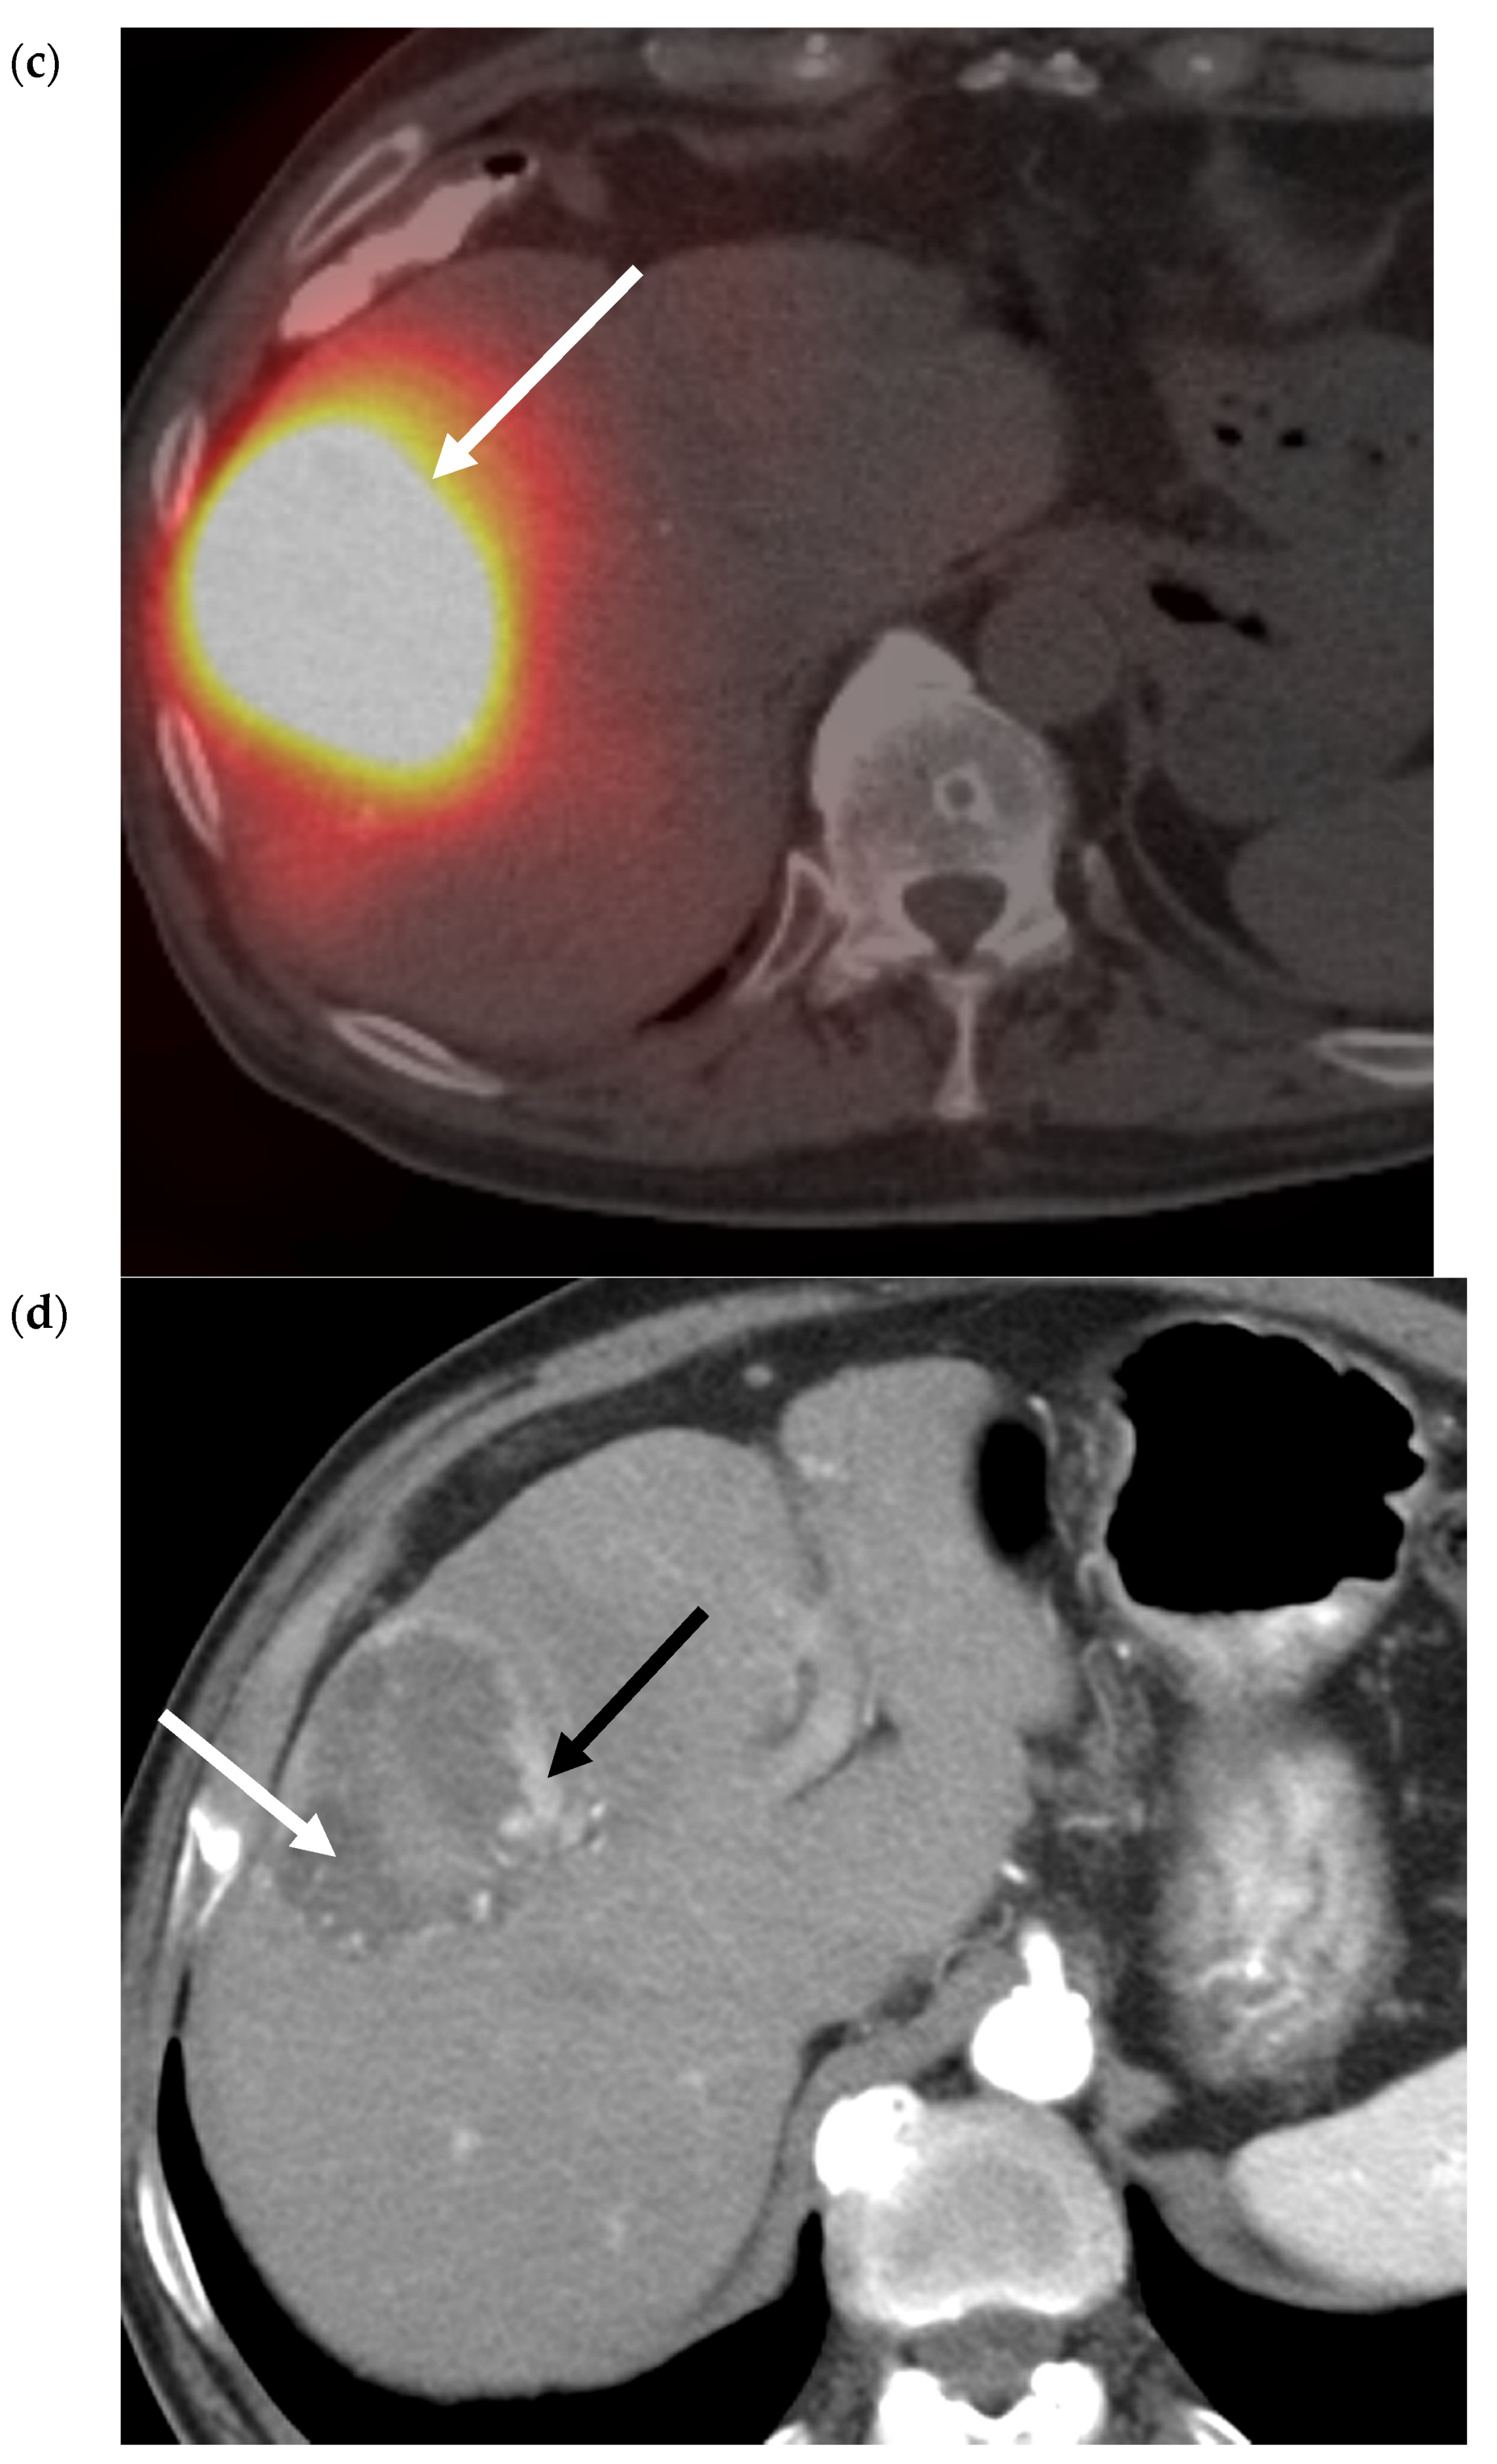

- Vouche, M.; Lewandowski, R.J.; Atassi, R.; Memon, K.; Gates, V.; Ryu, R.K.; Gaba, R.C.; Mulcahy, M.F.; Baker, T.; Sato, K.; et al. Radiation lobectomy: Time-dependent analysis of future liver remnant volume in unresectable liver cancer as a bridge to resection. J. Hepatol. 2013, 59, 1029–1036. [Google Scholar] [CrossRef]

- Teo, J.-Y.; Allen, J.C.; Ng, D.C.; Choo, S.-P.; Tai, D.W.; Chang, J.P.; Cheah, F.-K.; Chow, P.K.H.; Goh, B.K.P. A systematic review of contralateral liver lobe hypertrophy after unilobar selective internal radiation therapy with Y90. HPB 2015, 18, 7–12. [Google Scholar] [CrossRef]

- Labgaa, I.; Tabrizian, P.; Titano, J.; Kim, E.; Thung, S.N.; Florman, S.; Schwartz, M.; Melloul, E. Feasibility and safety of liver transplantation or resection after transarterial radioembolization with Yttrium-90 for unresectable hepatocellular carcinoma. HPB 2019, 21, 1497–1504. [Google Scholar] [CrossRef]